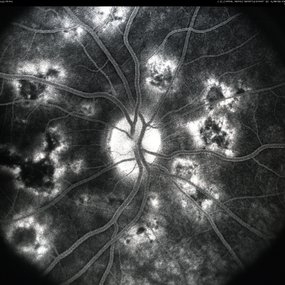

APMPPE Late Stage Scar Formation

Feb 27 2013 by Henry J. Kaplan, MD

APMPPE late stage scar formation. F/A hypofluorescence in the lesions area is due to masking effect of pigments . #1

Condition/keywords: acute posterior multifocal placoid pigment epitheliopathy (APMPPE), late stage, white dot syndrome